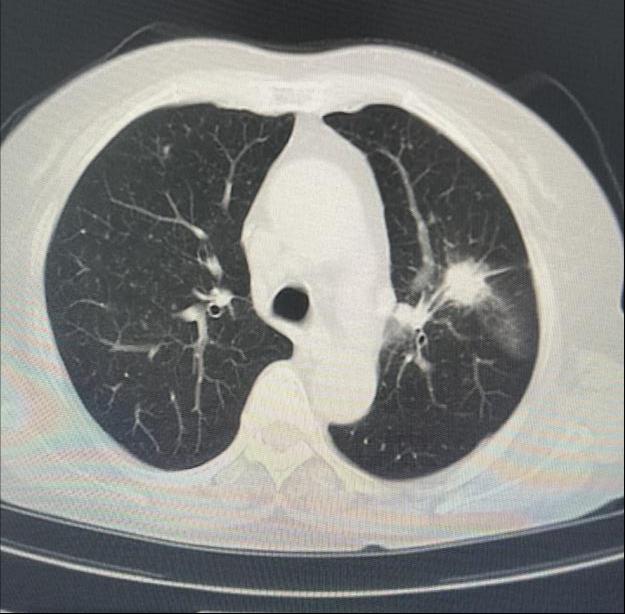

患者女性,因“气短1月”来门诊就诊,为明确诊断进一步治疗,收入呼吸与危重症医学科。入院后完善相关检查,胸部CT示左肺上叶前段高密度灶,与家属充分沟通后,决定为患者行超声支气管镜检查。主任医师吴水淼与主管护师薛冬冬为患者行气管镜检查,镜下示:双肺支气管均未见明显异常,结合CT给予超声探查,于左肺上叶前段亚支探及偏心异常回声区,由于亚支位置较高且管腔较窄,活检钳无法到达,给予冷冻肺活检。此次检查过程顺利,成功获取2块活检标本,活检病理结果提示为粘液腺癌。